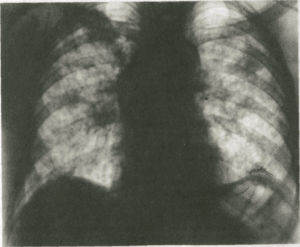

Хронический альвеолит может развиваться после повторных приступов острого альвеолита или начинается с прогрессирующей одышки от напряжения. Физикальные данные могут быть скудными или вообще отсутствовать. Пальцы в виде барабанных палочек развиваются редко и дыхательные шумы, как правило, в норме. Вентиляция легких нарушается по рестриктивному типу, изменяется газообмен и иногда возникает обструкция воздухоносных путей, что является следствием вовлечения в процесс бронхиол. Рентгенограмма грудной клетки показывает фиброзные тени в основном в верхних отделах.

• Рентгенологическое исследование •• При остром ГП изменения в лёгких выявляют в 30–49% случаев (часто изменчива) ••• Диффузная интерстициальная инфильтрация с затемнением базальных отделов ••• Нежные округлые тени размером от 1–3 мм и более ••• Усиление и деформация лёгочного рисунка ••• Пневмофиброз •• При хроническом ГП ••• Усиление лёгочного рисунка, двусторонние пятнисто-очаговые или узелковые инфильтраты ••• При прогрессировании болезни — диссеминация процесса ••• Прикорневая лимфаденопатия, плевральный выпот или пневмоторакс не характерны ••• В 40–50% случаев в верхних долях превалируют округлые тени и бронхоэктазы.